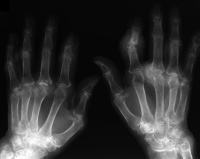

| Case 2. Tophaceous gout

with multiple joint involvement and carpal tunnel syndrome. |

| Right hand tophi involved

the extensor mechanism and a painful unstable index PIP joint. |

| Dorsal tophi diffusely

involved extensor mechanism, joint capsule and MCP joints. |